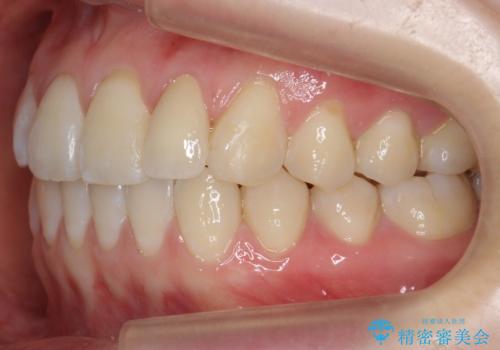

前歯が気になる 大人のマウスピース矯正 矮小歯を整える

- 前歯の並びを主訴に来院。

マウスピースで歯を抜かずに治療しています。

左上の前歯が飛び出しており、唇が笑った時に引っかかっていたのが解消しています。

左上の前歯は小さいため、(矮小歯)左右対称になるようにセラミックで形を修正する治療も併用しています。

歯を大きくかぶせるスペースを作るため、右上の奥歯を後ろに下げています。

左にずれていた上の正中も揃い、大変喜んでいただきました。